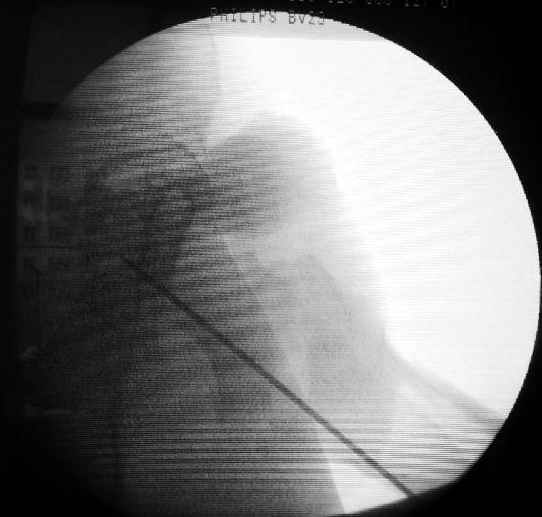

Как раз недавно у меня был примерный случай: больному 36 лет, поступил ночью, травма в результате мотоциклетной аварии, кроме чрезвертельного и спирального перелома левого бедра имеется переломы костей предплечья с этой же стороны. Скелетное вытяжение, а на следующий день больной про оперирован на ортопедическом столе с дистракцией. Чтобы не расколоть чрезвертельный перелом провели временную спицу ближе к переднему кортексу, из малого разреза костодержатель для репозиции, а фиксацию провели антиградным штифтом. Этапы операции на снимках.

DK> Чтобы не расколоть чрезвертельный перелом провели временную спицу

DK> ближе к переднему кортексу,